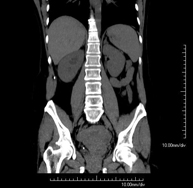

- Pelvis CT

Diagnostic test that involves obtaining high-definition anatomical two- and three-dimensional images of the pelvis (bone structures, vascular structures, bladder, uterus and ovaries, prostate and seminal vesicles, ureters, etc.) using CT (computed tomography) equipment. Most studies require the use of iodinated contrast.